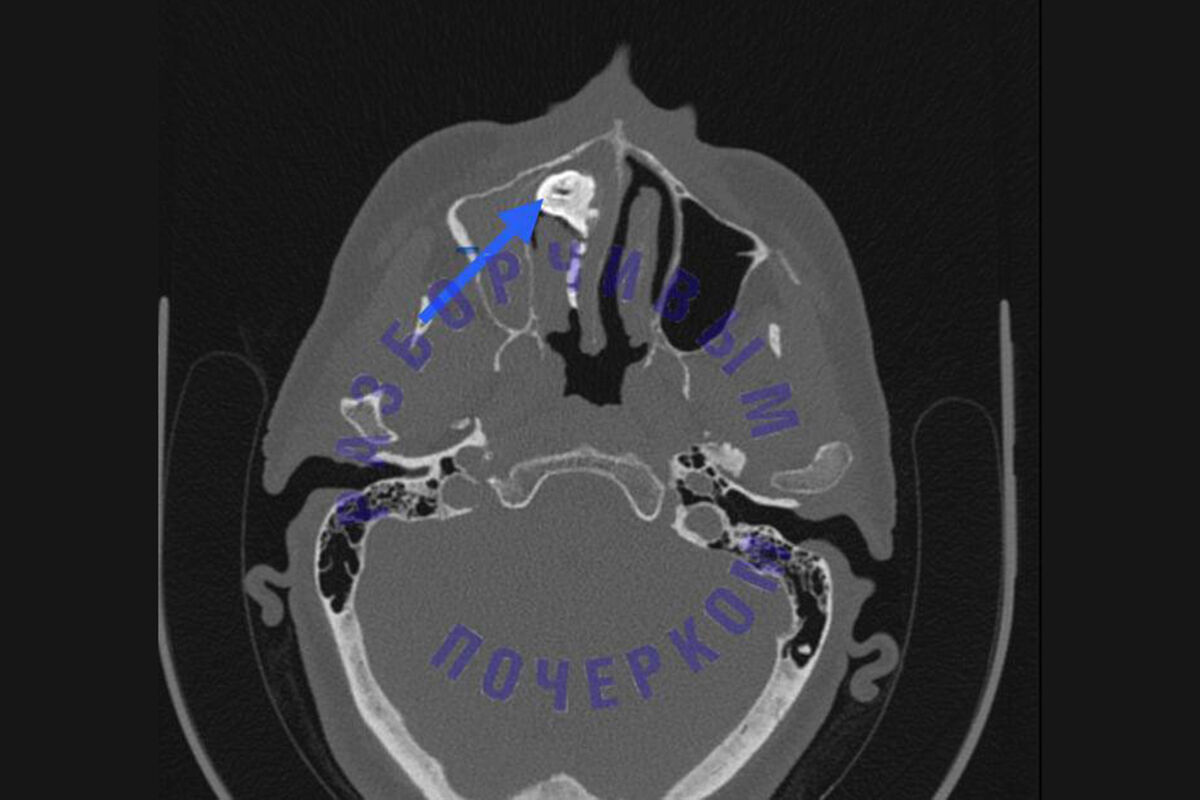

В Подмосковье врачи достали из носа пациентки закаменевшее инородное тело размером с перепелиное яйцо. Об этом сообщает Telegram-канал «Разборчивым почерком».

По информации Telegram-канала, жительница города Пушкино обратилась в больницу имени профессора Розанова В.Н. с жалобами на затрудненное дыхание, неприятный запах из ноздри и боль. Врачи в ходе диагностики установили, что в носовой пазухе пациентки находится ринолит — это закаменевшее инородное тело, которое образуется из-за долгого ослизнения. Женщина рассказала, что несколько лет назад ей что-то попало в нос, однако она не придала этому значения в связи с тем, что тревожные симптомы отсутствовали.

Вытащить ринолит целиком оказалось невозможно, и врачи решили предварительно раздробив его, извлечь инородное тело по частям. После удаления мешавшего женщине образования ее носовое дыхание восстановилось, а боль и выделения прекратились. Пациентку выписали из больницы.